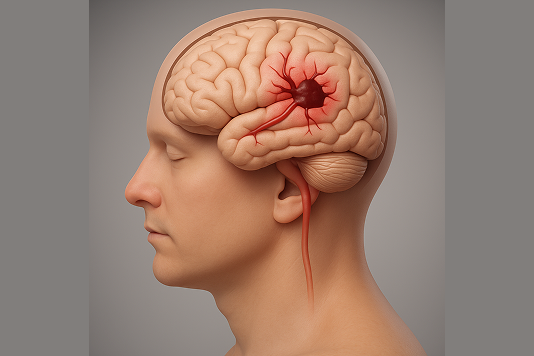

A stroke occurs when the blood supply to part of the brain is interrupted or reduced, preventing brain tissue from getting oxygen and nutrients. Brain cells begin to die within minutes.